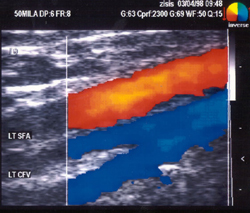

ΜΕ ΣΥΣΚΕΥΗ ΕΓΧΡΩΜΟΥ - DUPLEX (TRIPLEX)

Η απεικόνιση έγχρωμης ροής αποτελεί το τελευταίο επίτευγμα στον κατάλογο των

τεχνικών μη αιματηρής διάγνωσης των αγγειακών παθήσεων. Η συσκευή έγχρωμης ροής

(TRIPLEX) χρησιμοποιεί probe γραμμικής δέσμης 7,5MHz για τα επιπολής αγγεία

ή 5MHz για τα εν τω βάθει αγγεία. Η αιματική ροή κωδικοποιείται ως έγχρωμη (κόκκινη

ή μπλε), αναλόγως της σχέσης της με τον προσανατολισμό της ηχητικής δέσμης.

Ο κορεσμός του χρώματος και για τις δύο κατευθύνσεις (αρτηριακή ή φλεβική ροή)

είναι ένδειξη της ταχύτητας. Σε χαμηλές ταχύτητες, το χρώμα που απεικονίζεται

είναι σκοτεινό κόκκινο ή μπλε και καθώς η ταχύτητα αυξάνει, το χρώμα γίνεται

προοδευτικά φωτεινότερο, ούτως ώστε να καταστεί σχεδόν άσπρο στις υψηλότερες

ταχύτητες. Τα πλεονεκτήματα της μεθόδου TRIPLEX, σε σχέση με την κλασική DUPLEX

εξέταση, είναι τα εξής: α) καλύτερος εντοπισμός του αγγείου και επομένως ταχύτερη

διενέργεια της εξέτασης, β) με τη B mode εξέταση, η σοβαρότητα πολλών στενωτικών

αλλοιώσεων συχνά υποεκτιμάται λόγω ομοίων ακουστικών χαρακτηριστικών προσφάτου

θρόμβου αίματος και αιματικής ροής, γ) καλύτερη εξακρίβωση διεύθυνσης αιματικής

ροής, δ) διαπίστωση διαταραχών της ροής, όπως του στροβιλισμού και ε) αποτελεσματικότερη

εντόπιση μικρών αγγείων. Χρησιμοποιώντας συσκευές με τις ανωτέρω δυνατότητες

είναι σχετικά εύκολο, διαθέτοντας την ανάλογη εμπειρία, να διαγνωστούν οι διάφορες

παθήσεις των φλεβών των κάτω άκρων και γενικότερα του φλεβικού συστήματος.